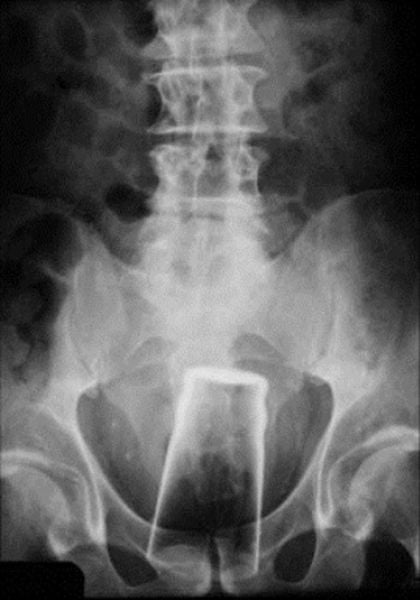

And the old classic: Pint Glass Up The Butt!